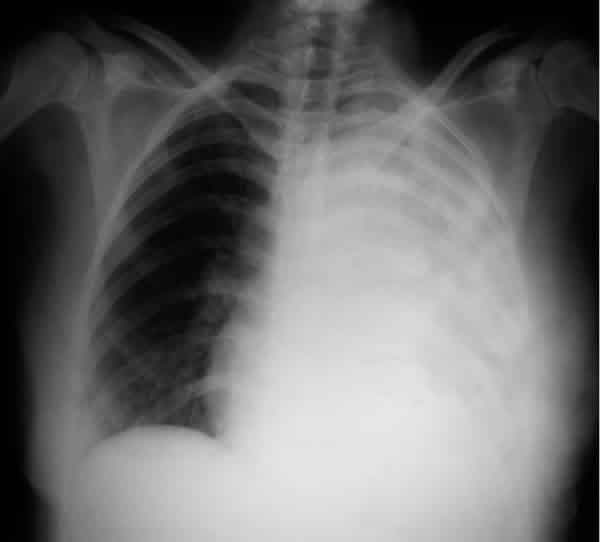

El mismo día que fue explorada en nuestro servicio, fue remitida al Servicio de Urgencias por haber debutado esa misma mañana con una disnea severa, le fue detectado un importante derrame pleural (fig. 3). Fue ingresada para ser estudiada y en el curso de apenas dos semanas se precipitaron los síntomas sistémicos debido a la enorme diseminación del tumor primario. El análisis histológico de una muestra obtenida mediante una broncoscopia, permitió identificar a un Carcinoma de Células Grandes pulmonar como tumor primario responsable de los múltiples focos metastásicos que la paciente presentaba y que en ese momento comprendía, además de la afectación ocular y torácica, masas cerebrales y hepáticas (figs. 4-6).

Fig. 3. Radiografía de tórax realizada a la

paciente el mismo día que fue explorada en nuestro Servicio, se puede apreciar

un derrame pleural masivo.